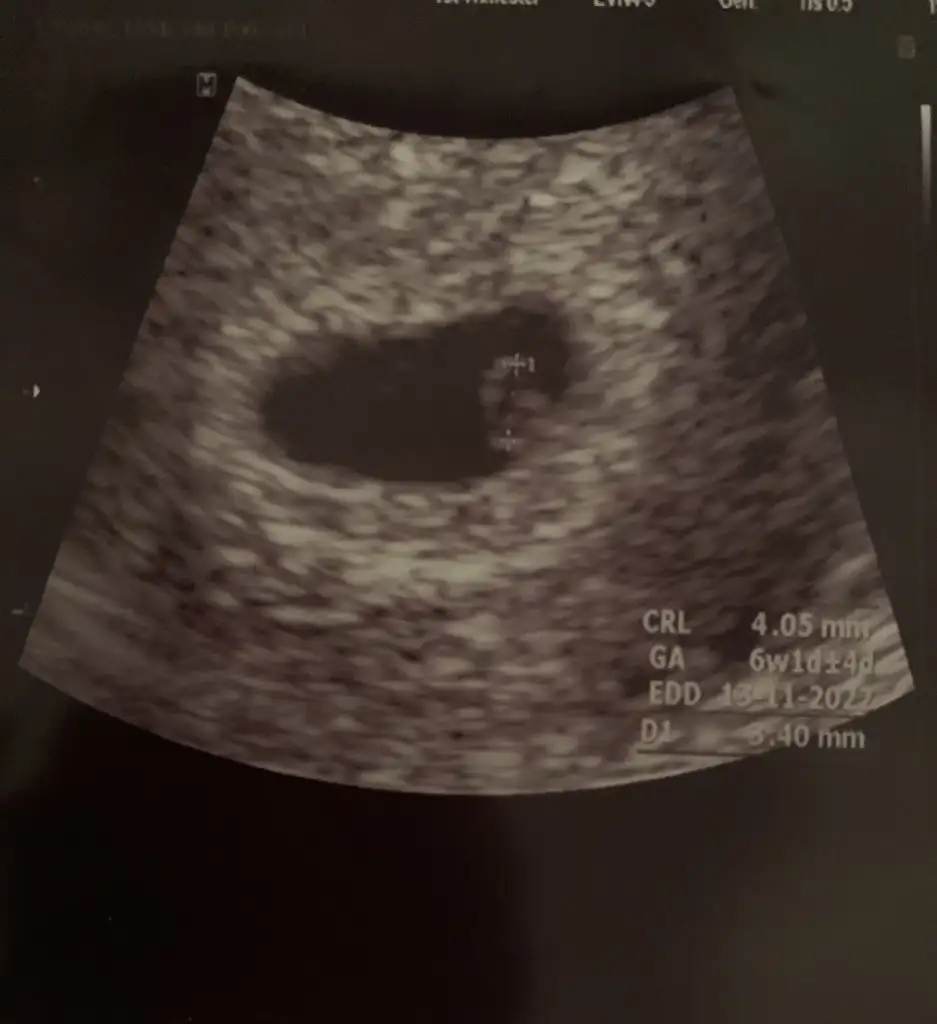

Benm 6+2 haftalik. Karından ultrasondan bakıldı. Bende merak ettim. Tahminin nedirSelam Kızlarbir çok kişi gruplardan beni bilir. Yine yetiştim imdatlara

kuzucum maşallah minicikBenm 6+2 haftalik. Karından ultrasondan bakıldı. Bende merak ettim. Tahminin nedir